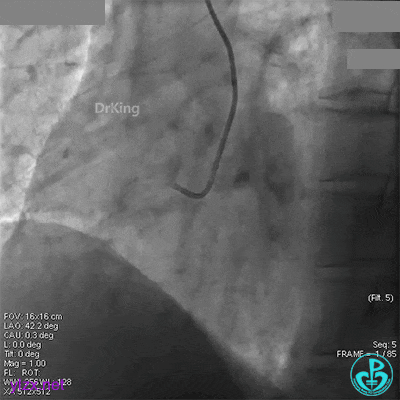

近端串联植入3.5×23mm支架后造影,前向血流没有恢复,患者感胸痛明显。

经刺破球囊冠脉内推注硝普钠后血流恢复2级,远端分支血管没有充分显影。